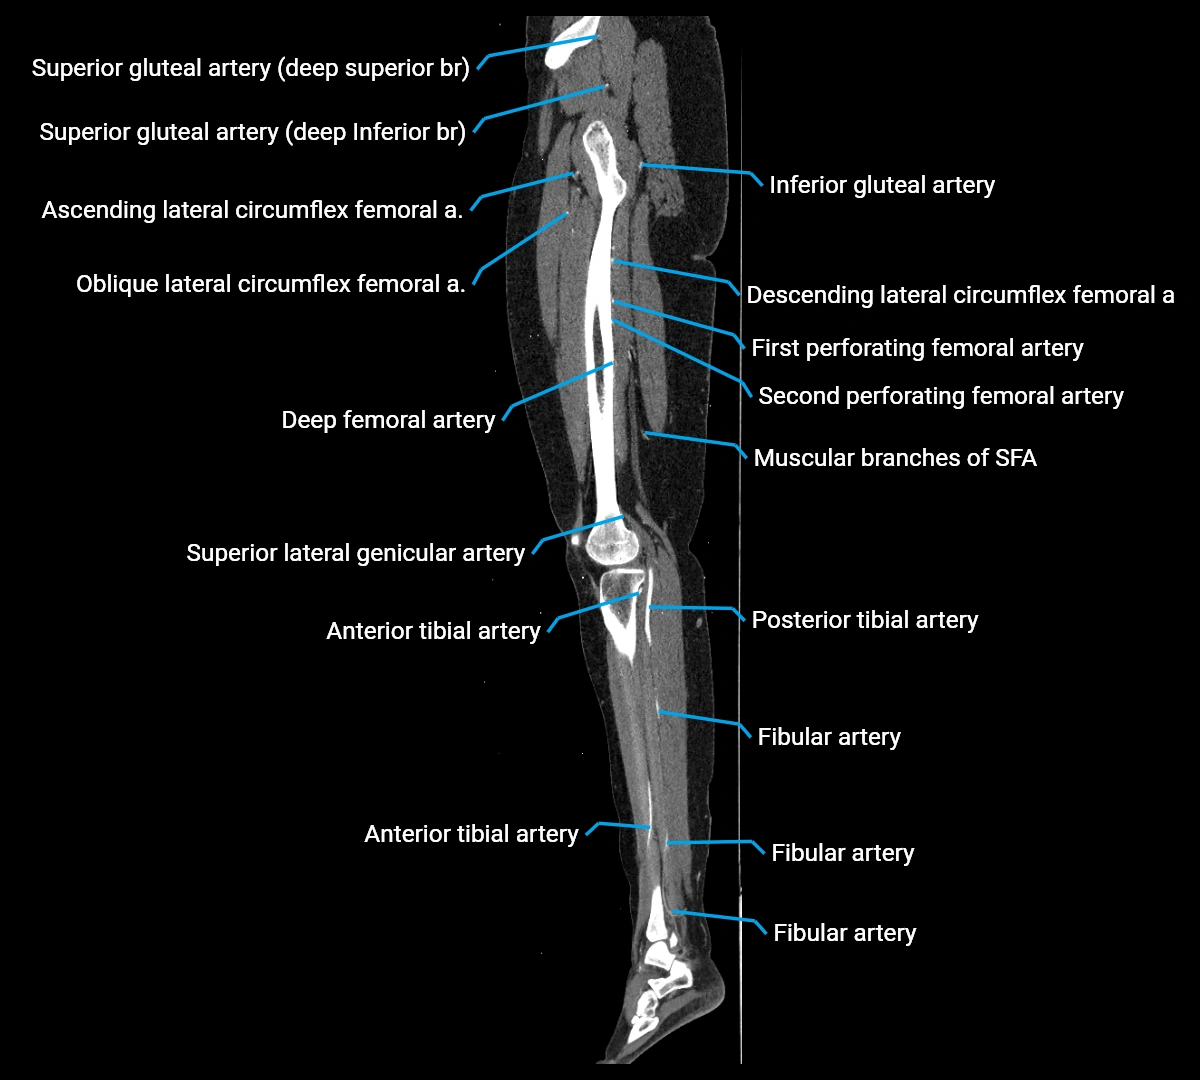

Contrast-enhanced CT (CTA):

• Gold standard for abdominal aortic imaging

• Provides excellent detail of lumen, wall, aneurysm, thrombus, and branch vessels

• Multiplanar and 3D reconstructions help in aneurysm measurement, stent graft planning, and dissection evaluation

• Detects acute rupture, traumatic injury, or occlusion with high sensitivity